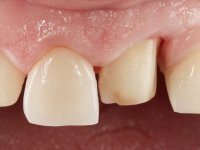

Paciente do sexo feminino, com 47 anos não fumadora. Apresentou-se na consulta com o dente 1.3 com tratamento endodôntico e com um espigão falso coto fundido, reabilitado com uma coroa provisória. Os dois incisivos laterais superiores são conoides e de reduzida dimensão. O dente 2.2 apresenta mobilidade, consentânea com uma significativa reabsorção óssea entre o dente 2.1 e o dente 2.3 Os dois incisivos centrais estão separados por um diastema de 3mm e o dente 2.3 apresenta uma oclusão cruzada com o dente antagonista. Verifica-se também a ausência de alguns dentes posteriores e uma higiene oral razoável. Na segunda intervenção realizada passados 8 anos, verificou-se que os incisivos centrais superiores se apresentavam cromaticamente mais escuros e apresentavam um sulco longitudinal no esmalte que estando pigmentado comprometia esteticamente o sorriso. O trabalho realizado na primeira fase do tratamento mostrava-se competente estética e funcionalmente. Por fim, um ano após a última intervenção, a paciente apresentou-se com uma fratura da faceta colocada no dente 2.1 provavelmente em resultado de estar em contacto com o coto do implante. A rigidez da anquilose implantar, pode ter sido a causa desta fratura. Outros casos deste tipo de fratura já foram observados por mim em situações clínicas idênticas. A faceta do dente 1.2 apresentava-se esteticamente comprometida e a própria estrutura dentária apresentava uma pequena cárie e, pelo que se recomendaria a sua substituição.

O tratamento iniciou-se com a re -preparação do coto do espigão falso coto fundido, com o objetivo de colocar as linhas de acabamento cervical com uma localização intra-sulcular e simultaneamente confecionar uma coroa provisória adaptada. Com um tratamento ortodôntico muito simples, fechou-se o diastema entre os incisivos centrais superiores e estabilizou-se esta posição com um arame colocado na superfície palatina dos centrais, funcionando como contenção. Posteriormente procurou-se fazer uma tração ortodôntica lenta do dente 2.2 com o intuito de diminuir, ainda que muito ligeiramente a perda óssea vertical nessa zona. Finalizada a tração, foi feita a extração do dente 2.2 e a zona foi reabilitada provisoriamente com uma coroa de resina composta colada aos dentes adjacentes. Foi colocado um implante dentário na zona do dente 2.2 sendo novamente colada a coroa provisória em resina, reabilitando provisoriamente a paciente durante o período de osseointegração. No dente 1.3 foi feita uma gengivectomia com bisturi elétrico, com a intenção de subir o nível cervical do 1.3 conseguindo uma maior harmonia com o dente 2.3. Estabilizados os tecidos moles, foi feita uma impressão com a técnica de moldeira aberta, utilizando silicones de adição de consistência “putty” e “light”. A recolha da cor, tanto da componente dentária como dos tecidos moles foi feita pelo ceramista no consultório.  No laboratório as impressões foram passadas a gesso e deram origem a modelos de trabalho que foram devidamente analisados. Foi decidido confecionar um “abutment” metalo-cerâmico aparafusado sobre o implante. Este “abutment” foi fundido com uma liga nobre e posteriormente revestido a cerâmica coronária e gengival. Dada a inclinação do implante o aparafusamento condicionou de forma inevitável a saída do orifício do parafuso pela superfície vestibular. No sentido de esconder esta situação, o desenho do “abutment” já foi idealizado com a intenção de acomodar na superfície vestibular a colagem de uma faceta feldspática. Este “abutment” foi provado em boca e foram feitos ajustes no componente cerâmico gengival. A sua adaptação aos tecidos moles foi feita tanto de forma subtrativa, com broca, como de forma aditiva, acrescentando resina composta de tonalidade gengival. Este acrescento de resina seria orientador do ceramista na colocação final da cerâmica de tonalidade gengival. A coroa que reabilitaria o dente 1.3 foi cimentada nesta consulta de prova com cimento de ionómero de vidro reforçado com resina composta. Finalizado o trabalho em laboratório da faceta sobre o 1.2 e o “abutment” e a faceta para o implante este foi colado em boca, após a colocação do isolamento absoluto. O trabalho satisfez plenamente a paciente. Durante oito anos a paciente foi seguida regularmente, mostrando-se agradada com o tratamento efetuado, no entanto começou a mostrar interesse em intervir esteticamente nos incisivos centrais superiores. Decidida a segunda fase da nossa intervenção, foi feita a preparação dentária dos dentes 1.1 e 2.1 para a colocação de duas facetas feldspáticas. Particular cuidado foi tido na preparação inter-proximal distal junto ao “abutment” do implante. Foi preciso avaliar muito pormenorizadamente o eixo de inserção da faceta em relação ao “abutment”. As facetas feldspáticas foram confecionadas em laboratório e posteriormente coladas em boca após a colocação de isolamento absoluto. Um ano após, iniciamos a nossa terceira fase de tratamento, após a faceta colada no dente 2.1 ter fraturado. A preparação dentária foi feita sobre a faceta colada, procurando estender mais para palatino o interface inter-proximal distal. O objetivo seria passar para mais palatino do ponto de contacto o interface faceta-dente. O preparo dentário do dente 1.2 também foi muito reduzido, limitando-se a criar um eixo de inserção. Após confecionadas a coroa total e a faceta em laboratório foram coladas em boca. Primeiro foi colada a coroa utilizando-se um isolamento relativo com teflon, posteriormente foi colada a faceta após a colocação do isolamento absoluto. Na coroa utilizei este tipo de isolamento para evitar a utilização de grampos. Seria difícil de aplicar pela forma e dimensão do dente e agressivo para os tecidos moles. Após a colagem foi avaliada a integração oclusal do trabalho.